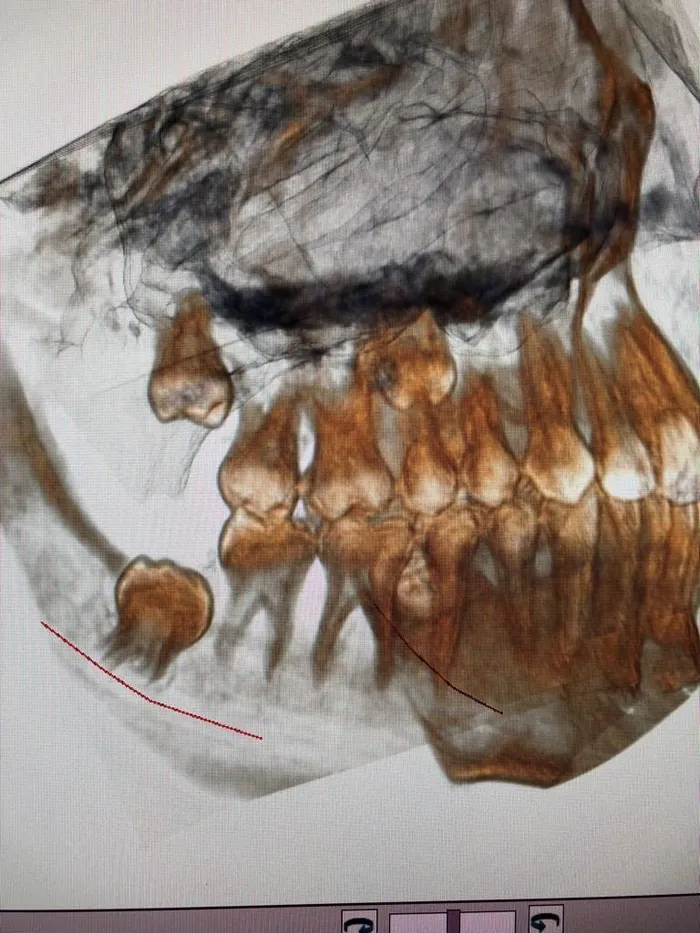

Procedure di chirurgia estrattiva

Prevede l’estrazione di elementi dentari o radici non più mantenibili in parziale o totale inclusione osteomucosa. Questa chirurgia riguarda spesso i denti del giudizio (“ottavi”) che per motivi di spazio o anatomici non erompono normalmente in arcata e rimangono parzialmente o totalmente inclusi (disodontiasi): quando creano fastidio o causano danni ai denti vicini è necessario estrarli.

Spesso questi denti, anche se in arcata, vanno estratti in quanto, essendo difficili da pulire, accumulano placca batterica determinando maggiore rischio di carie e danni parodontali.